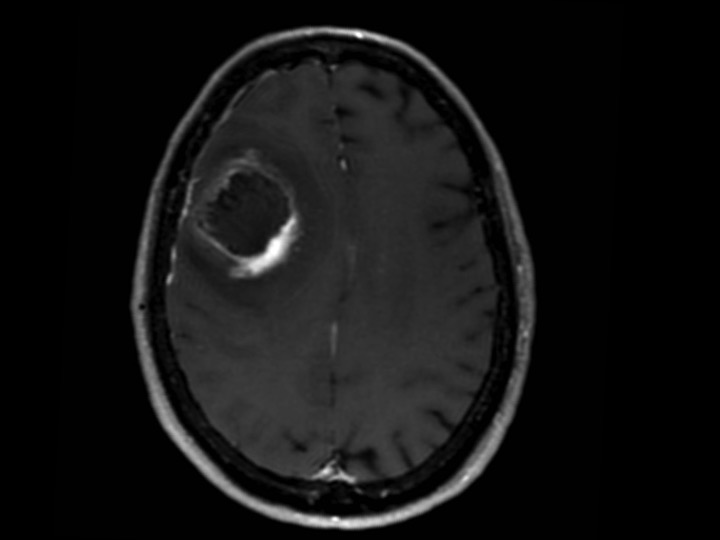

How reliable is MRI for the evaluation of treated high-grade gliomas?

In this meta analysis, the authors point out the potential weaknesses of “anatomical MRI” for evaluating the response to treatment. Conversely, the found that the added value of spectroscopy was high.

• Treatment response assessment in high-grade gliomas with anatomical MRI is unreliable